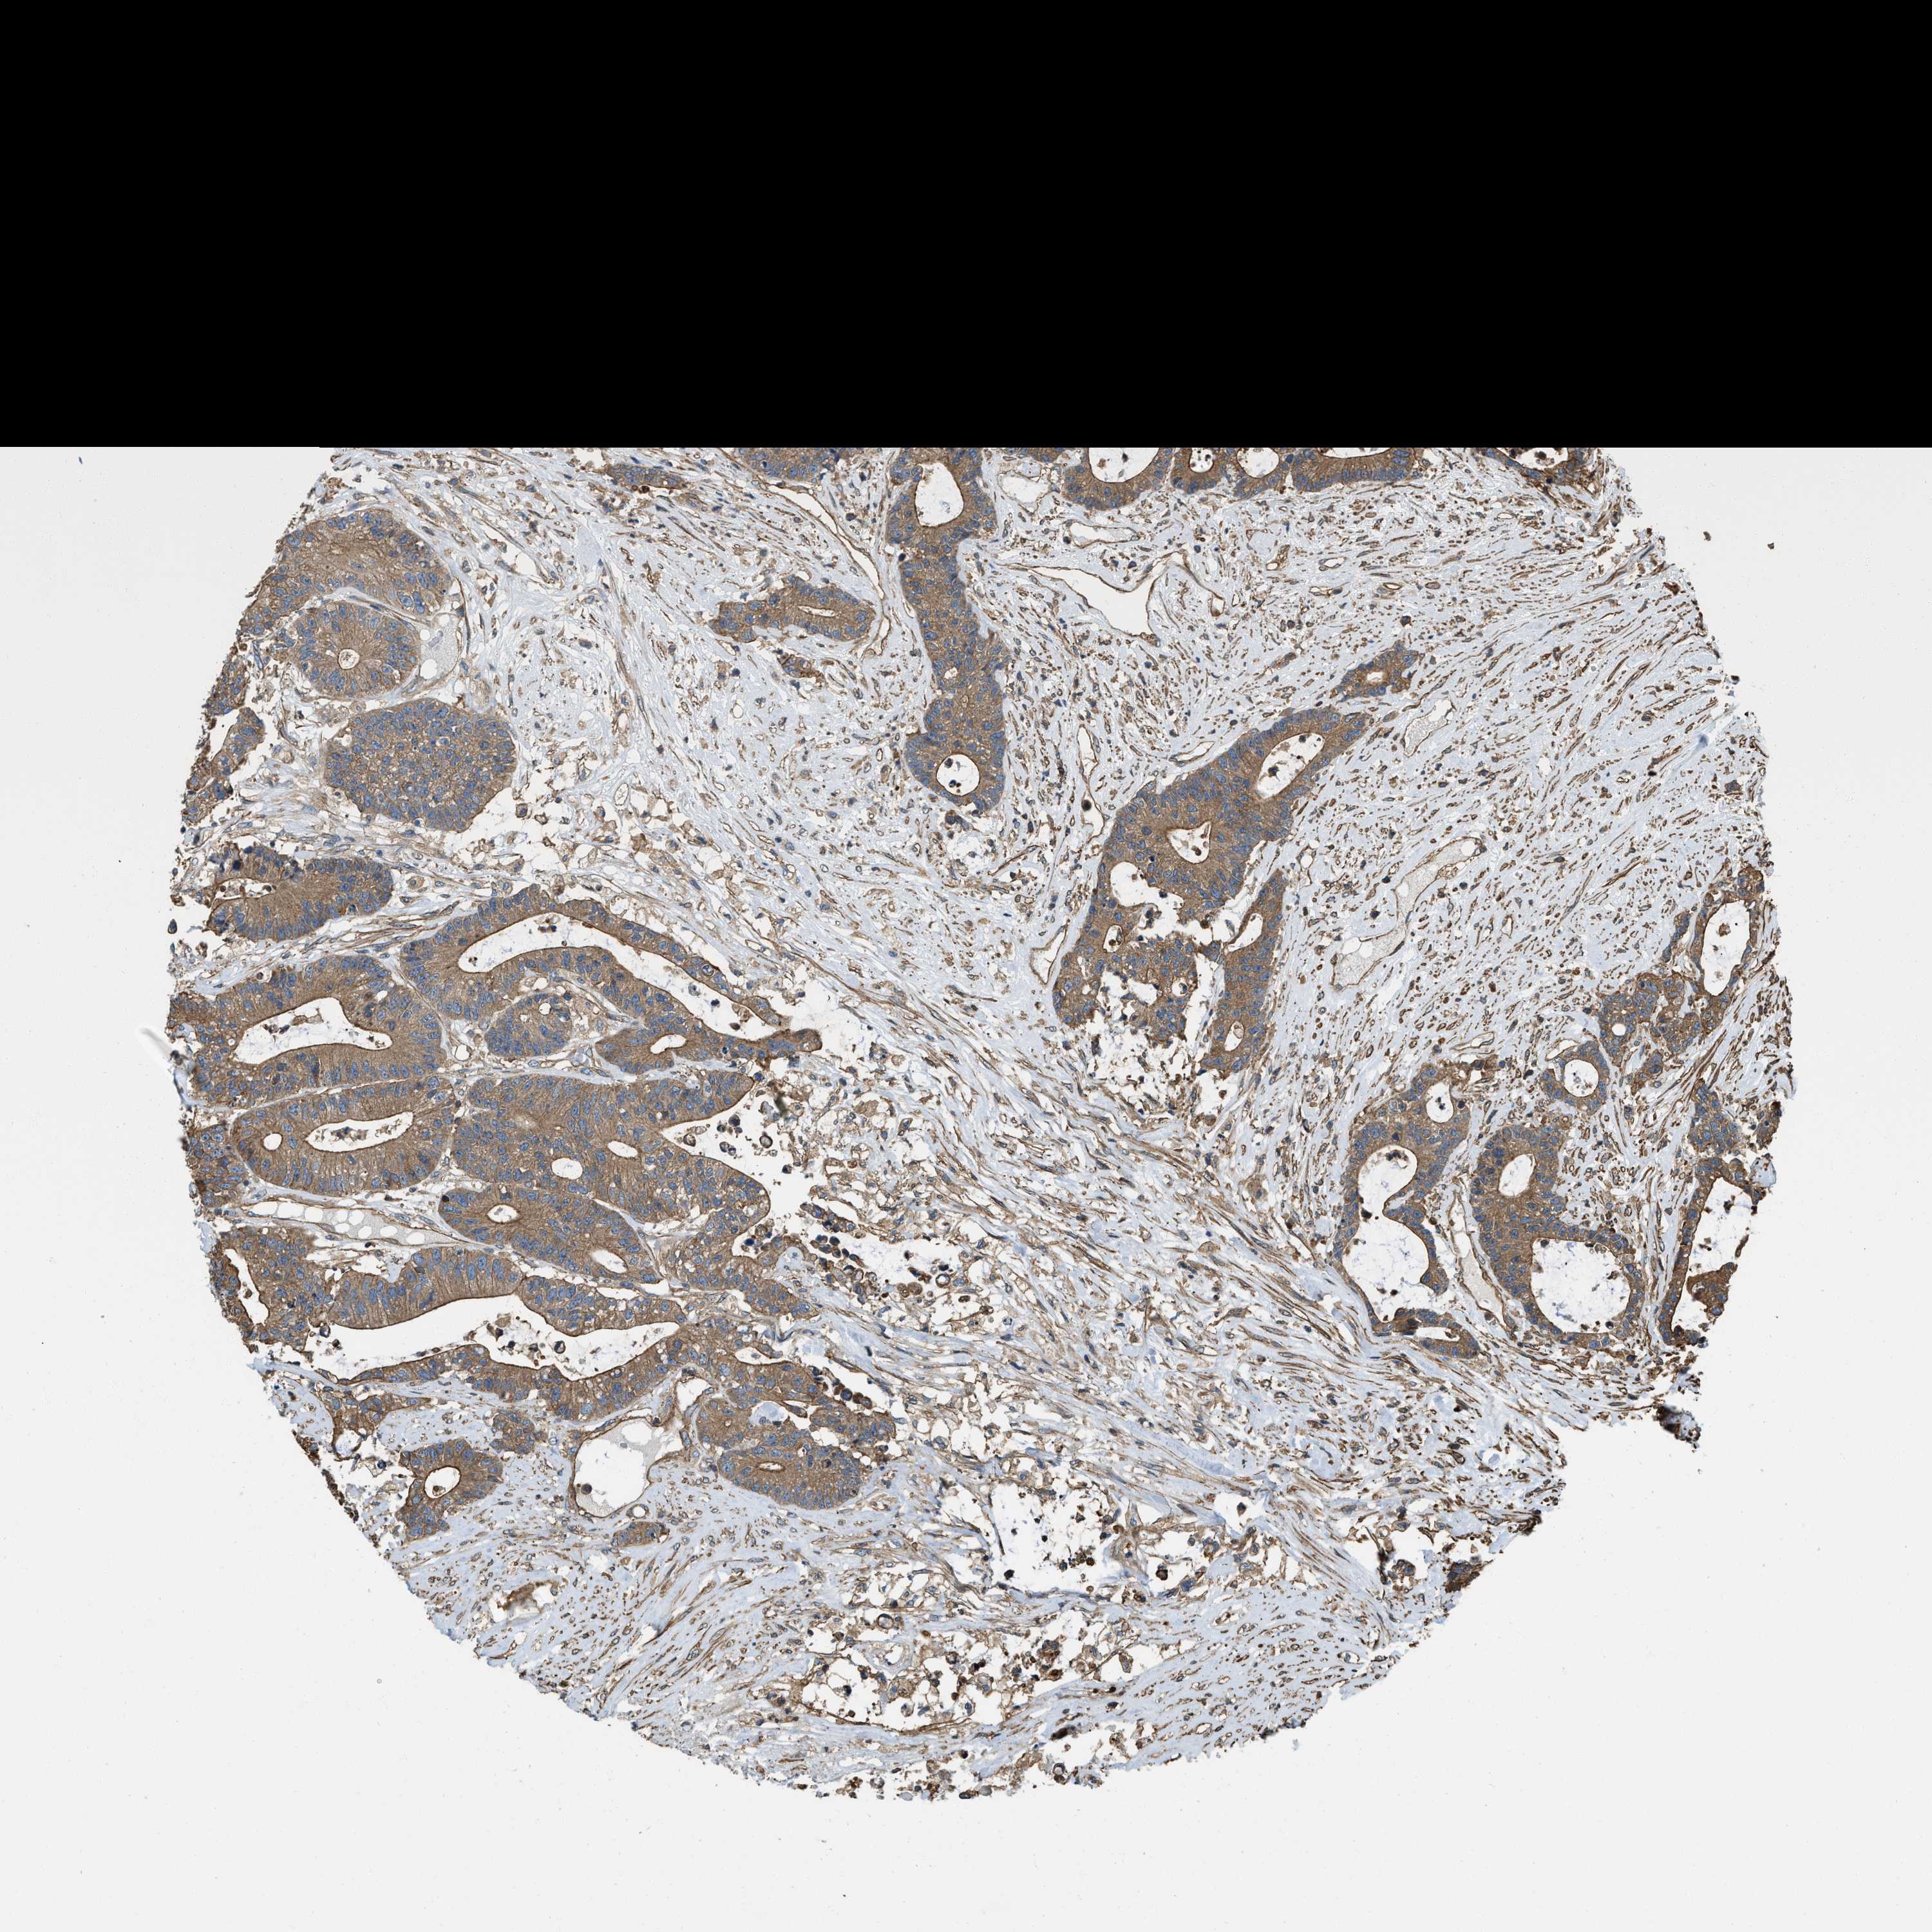

CANCER COLORECTAL CANCER Show tissue menu

COAD TCGA COAD VALIDATION READ TCGA READ VALIDATION PROTEIN COAD CPTAC PROTEIN EXPRESSION

ANTIBODIES

AND

VALIDATION